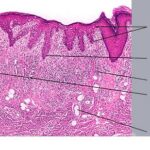

PATHOLOGY The intraepidermal adenocarcinoma of EMPD and MPD has a similar histologic appearance. There are groups, clusters, or single cells within the epidermis that show nuclear enlargement with atypia, prominent nucleoli, and well-defined ample cytoplasms . Intercellular bridges are absent. The cells can be within all levels of the epidermis and can compress but preserve the basal layer without junctional nest formation. The cells can extend into the contiguous epithelium of hair follicles and sweat gland ducts. Acanthosis, hyperkeratosis, and parakeratosis are often present. These cells have a “pagetoid” appearance and simulate other intraepidermal malignancies, including melanoma, pagetoid squamous cell carcinoma in situ, mycosis fungoides, cutaneous adnexal carcinomas (sebaceous carcinoma, porocarcinoma, and others), Merkel cell carcinoma, Langerhans cell histiocytosis, and other epidermotropic cutaneous metastases. The cells of MPD and EMPD can be pigmented, which should not necessarily indicate they are melanocytic. Paget's cells have intracellular mucopolysaccharides, with EMPD having a greater amount of mucin as compared